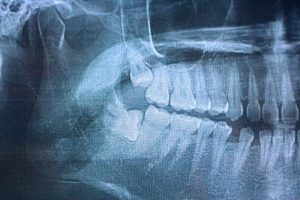

x-ray of impacted wisdom teethWisdom teeth extractions are surgical procedures that remove one or more third molars, commonly known as wisdom teeth, when they cause problems or pose risks to oral health. These teeth typically emerge between ages 17 and 25, but often lack adequate space in the mouth, leading to impaction, crowding, or other complications that require professional removal.

1. Initial Consultation and Examination: Dr. Smith or Dr. Cooper conducts a thorough evaluation, including digital X-rays or 3D imaging to assess tooth positioning, root development, and proximity to nerves and other structures.